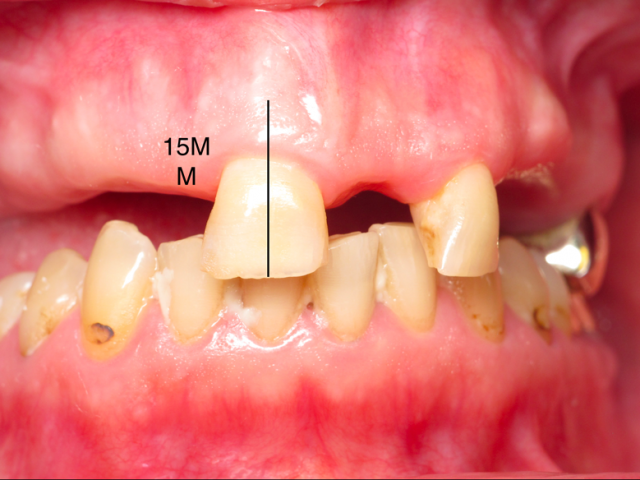

It is incredibly important for us to properly treatment plan these cases to mitigate potential risk and complications. Certainly the greatest risk is not providing enough prosthetic space. It is paramount the surgical team create enough vertical height from the implant level to the incisal edge of the prosthesis.

There has to be enough vertical height to stack components: abutments, Ti bar, the acrylic wrap and denture teeth. It is commonly reported in the literature that a minimum vertical height requirement is 15 to 16 mm from the fixture to the incisal edge.

It is possible to restore a case with only 13 mm, but careful coordination is required with the lab, and certain patient anatomic and occlusal relationships are required.

Using calipers set at 15 mm, I will measure from the incisal edge or buccal cusp tips and mark the alveolus. After the teeth are removed, then the bone reduction is completed down to the indicated marks, and I then have created the required space.